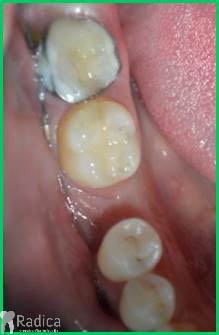

U dolje prikazanim slikama se vidi impaktirani drugi trajni premolar koji je resorbirao dio korijena i krune prvog trajnog molara. Pacijent se javio zbog jakih bolova u području molara koji je bio intaktan te je napravljen ortopantomogram. Molar se morao izvaditi i pacijent je trenutno u terapiji.